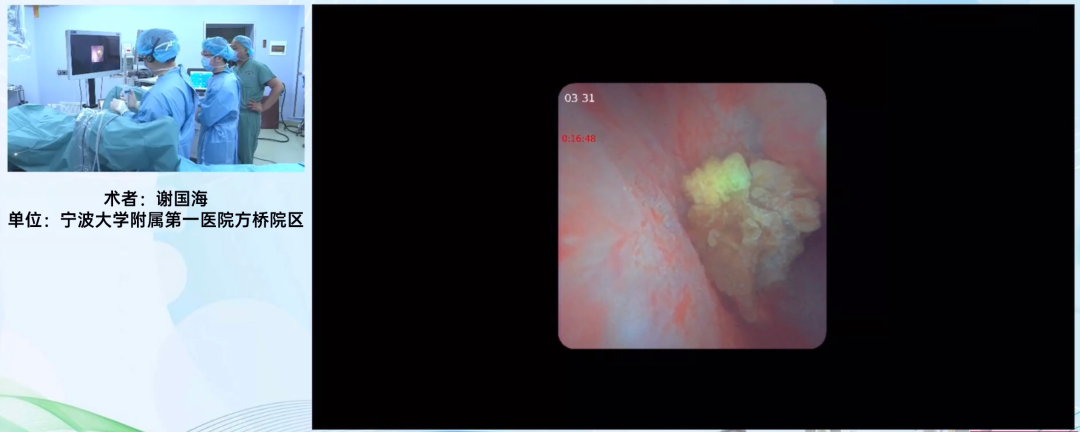

宁波大学附属第一医院方桥院区 谢国海教授

谢国海教授在线上手术演示中使用普生7.5Fr一次性输尿管软镜PU3033A配合12/14F负压可弯鞘及摩西激光进行碎石操作。

谢国海教授强调,普生这款一次性输尿管软镜手感极佳,其纤细程度超越了直观上7.5Fr的感知,镜鞘比优越,且镜体轻盈,能显著减轻术者疲劳。对比市面上同类型的细镜子,虽追求极致细径,却往往折衷了工作通道尺寸,导致终末端灌流量受限,无法持续维持术中视野清晰,而普生这款产品在术中展现了卓越的清晰度,其图像处理还原度高,为精准手术提供了优越条件。

目前临床针对支架管长期留置给患者带来的不适,开始逐渐减少支架的使用,而采用细镜与细鞘组合亦是减少支架留置的有效手段。对于留置了支架的患者,考虑复诊便利,谢国海教授通常建议患者保留两周,以便复查时同步完成支架拔除程序,此举体现了对患者恢复过程的人性化考量与技术应用的精细化管理。